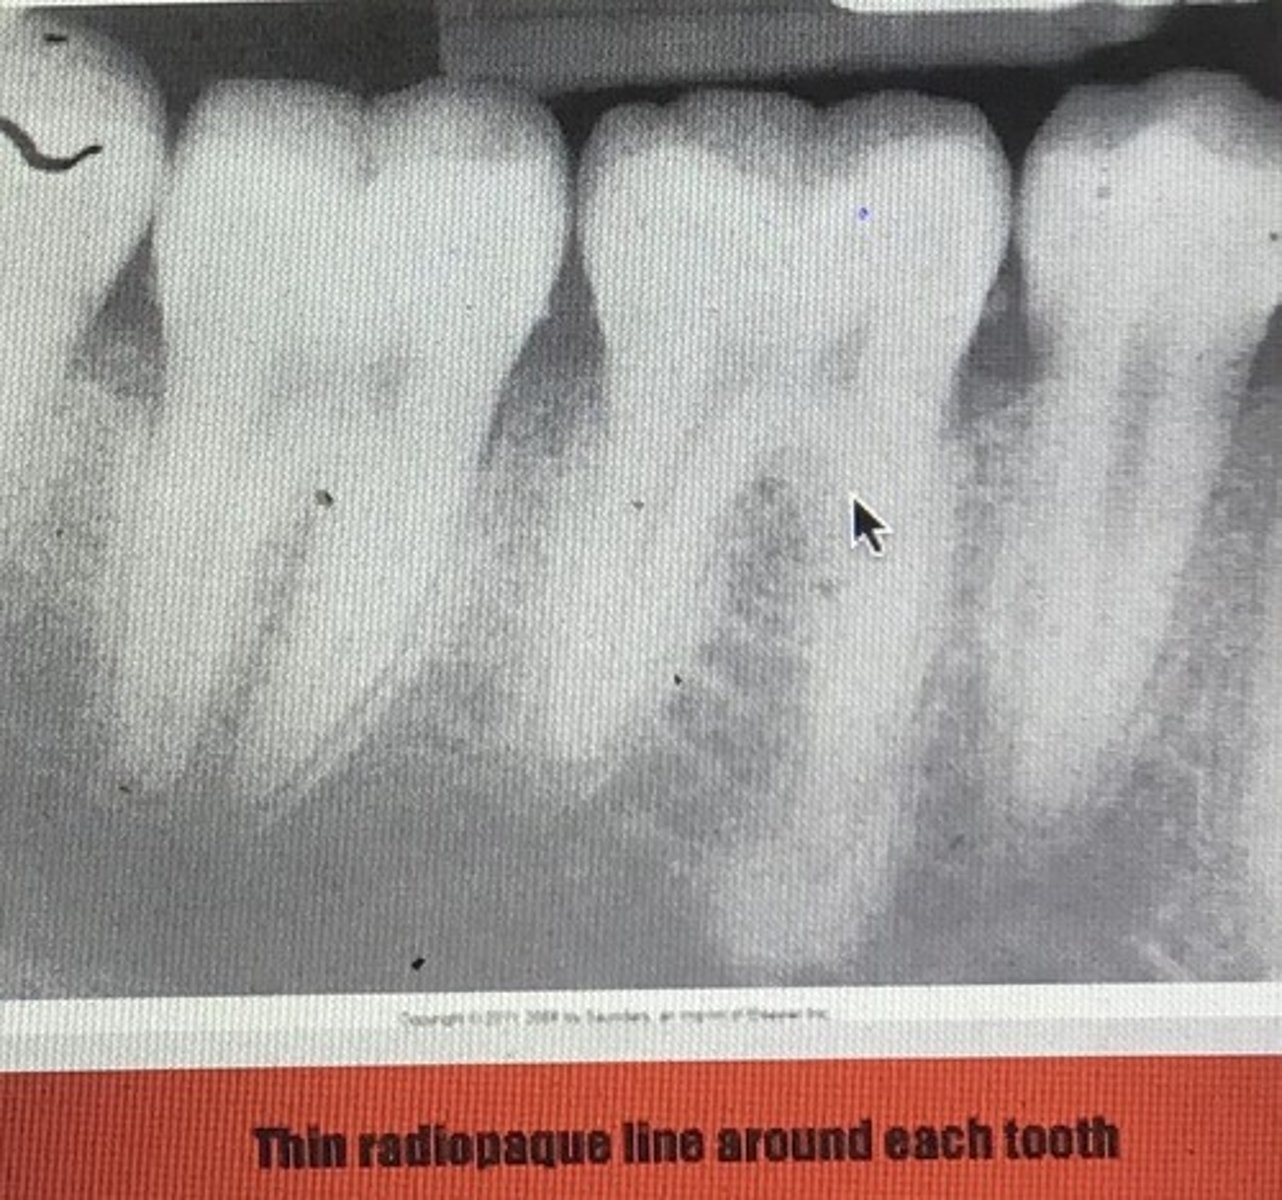

Alveolar bone proper/ cribiform plate/ lamina dura (radiographic name): type of bone that lines the sockets where roots sit

<p>Alveolar bone proper/ cribiform plate/ lamina dura (radiographic name): type of bone that lines the sockets where roots sit</p><p>- thin and compact</p><p>- small openings for vascularity</p><p>2 layers</p><p>- compact lamellar bone</p><p>- layer of bundle bone into which the periodontal fibers insert</p><p>* core of the fibers remain uncalcified in the calcified tissues of bone or cementum (sharpey’s fibers)</p>